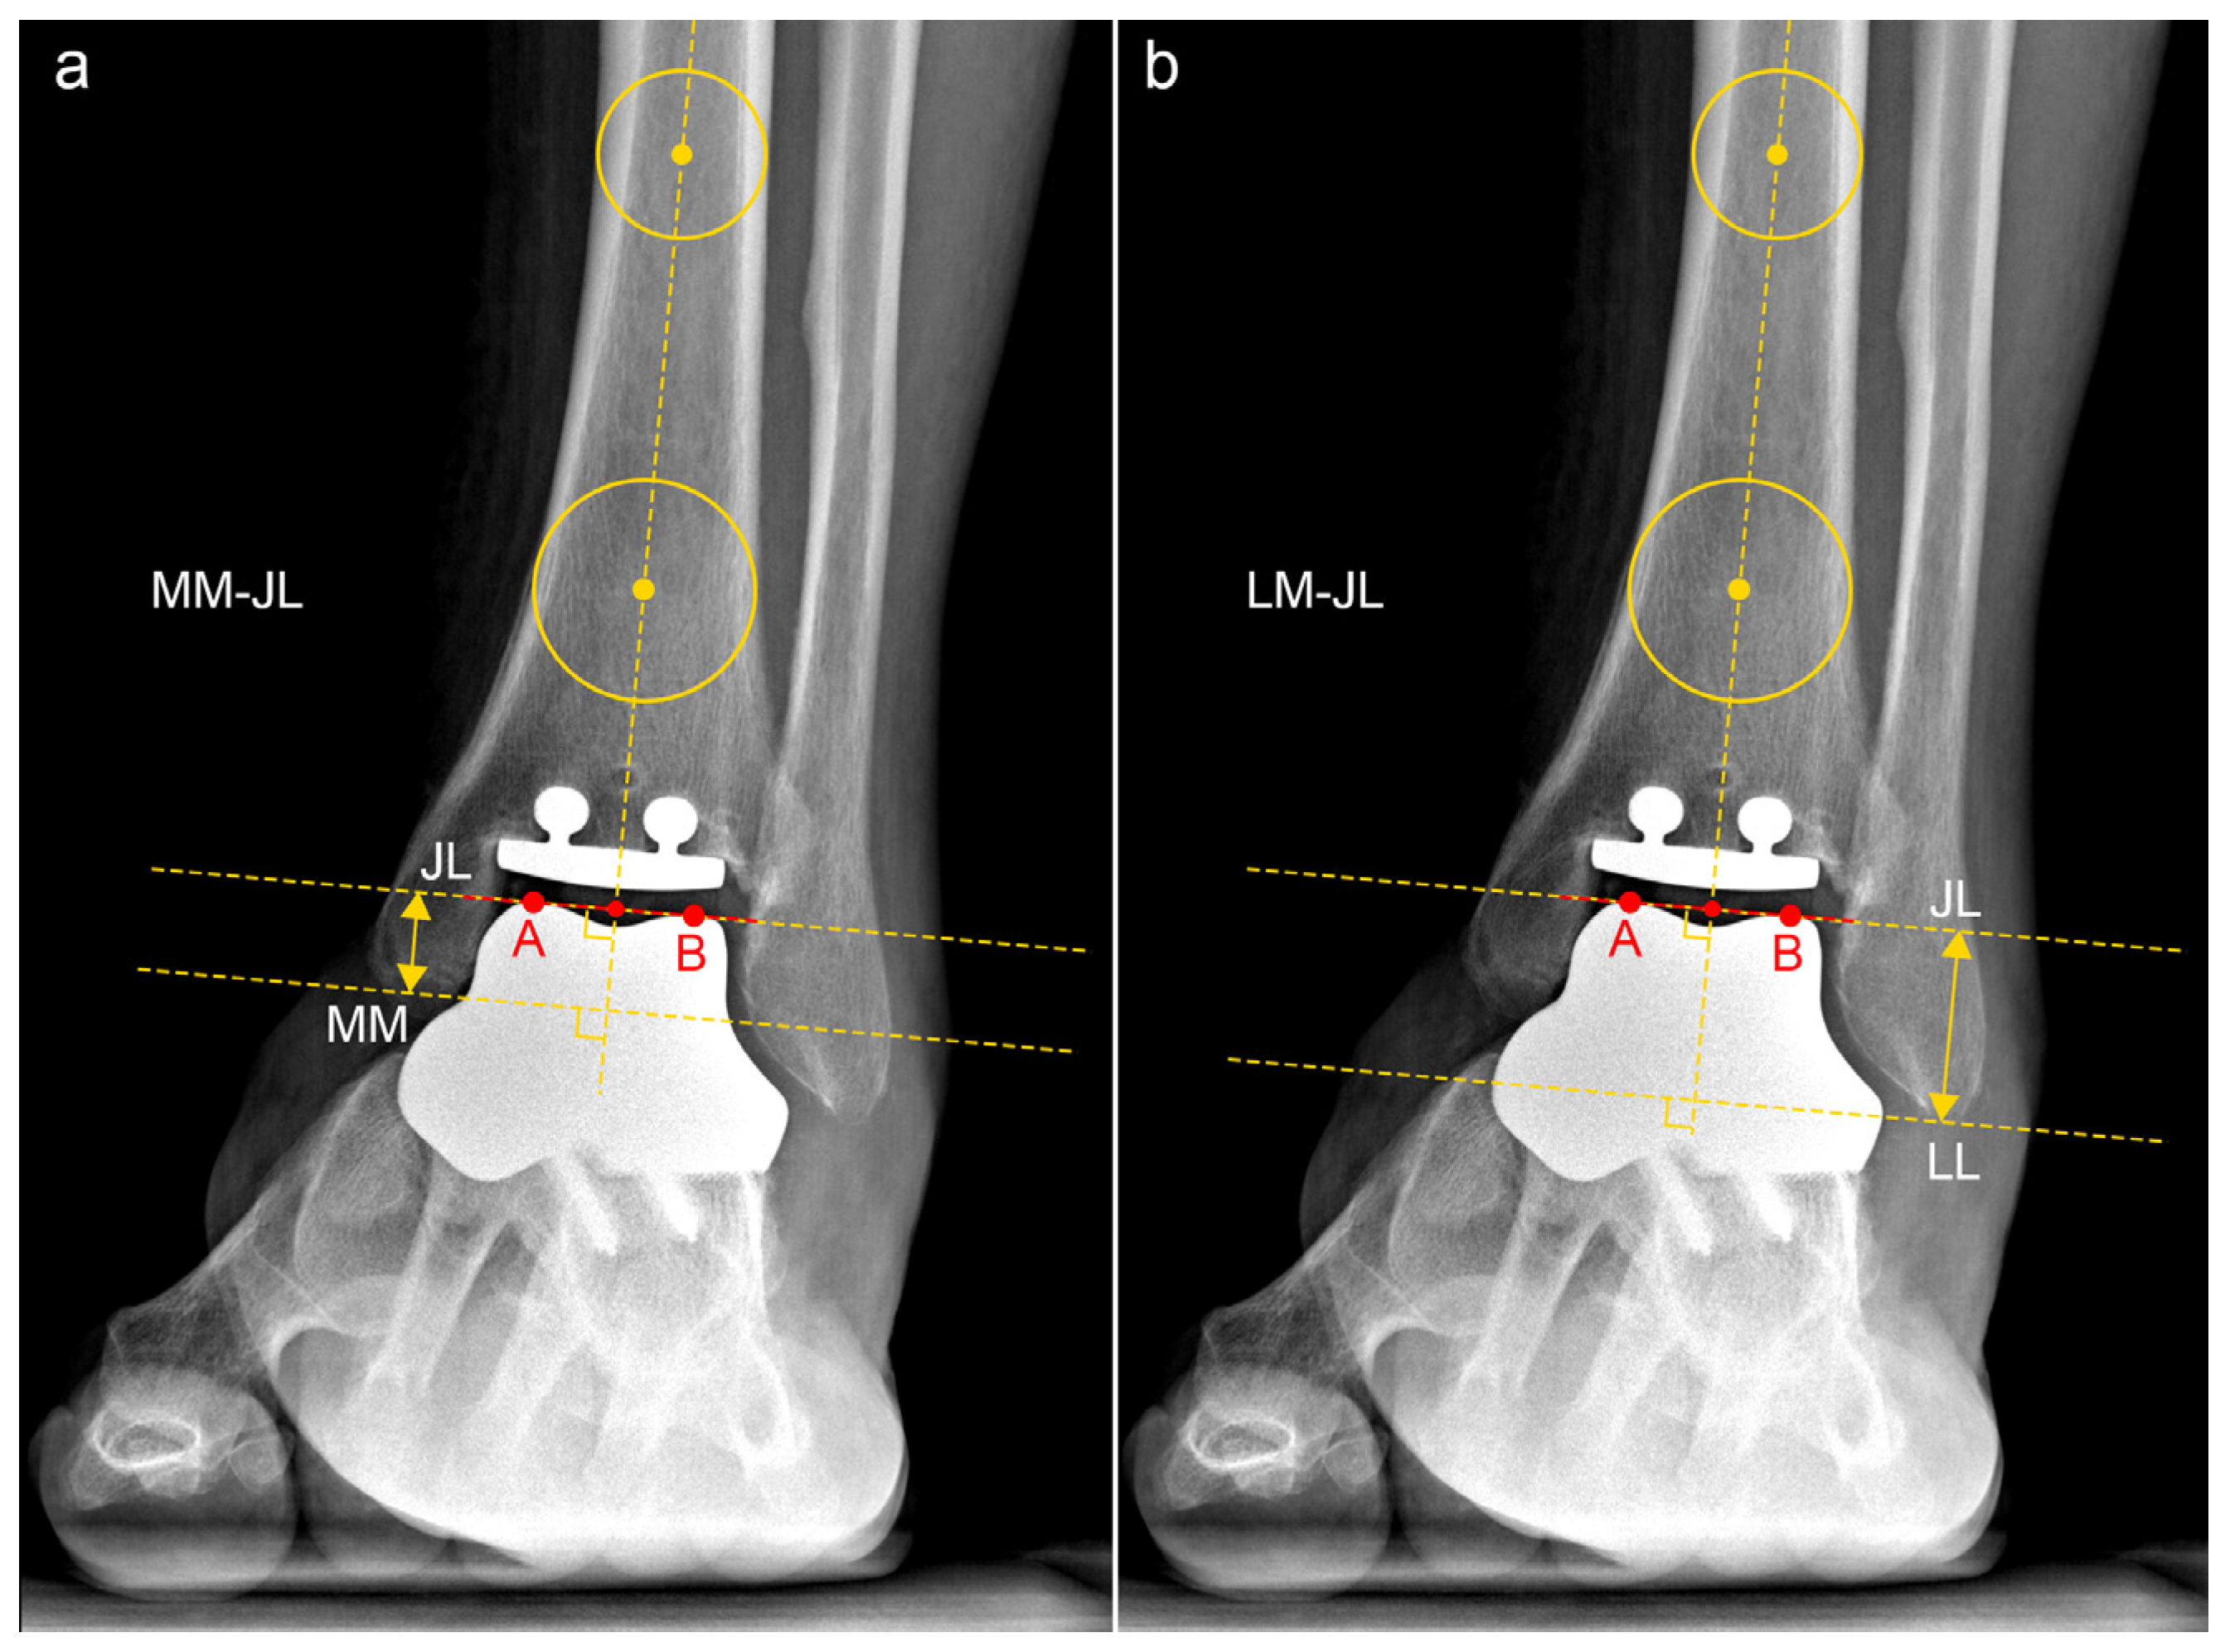

| JLHR 1 | 2.23 ± 0.54 | 1.94 | 1.64–3.44 | 24.3% |

| LM-JL 2 distance | 2.30 ± 0.39 cm | 2.12 cm | 1.78–3.19 cm | 17.0% |

| MM-JL 3 distance | 1.21 ± 0.30 cm | 1.11 cm | 0.89–1.78 cm | 24.9% |

| CS-JL 4 distance | 3.82 ± 0.51 cm | 3.87 cm | 2.94–4.53 cm | 13.4% |

| JLHR 1 (contralateral) | 1.95 ± 0.54 | 1.92 | 1.49–3.54 | 27.7% |

| LM-JL 2 distance (contralateral) | 2.21 ± 0.26 cm | 2.12 cm | 1.84–2.81 cm | 11.8% |

| MM-JL 3 distance (contralateral) | 1.00 ± 0.20 cm | 0.92 cm | 0.76–1.42 cm | 20.3% |

| CS-JL 4 distance (contralateral) | 4.04 ± 0.32 cm | 4.06 cm | 3.46–4.53 cm | 7.8% |